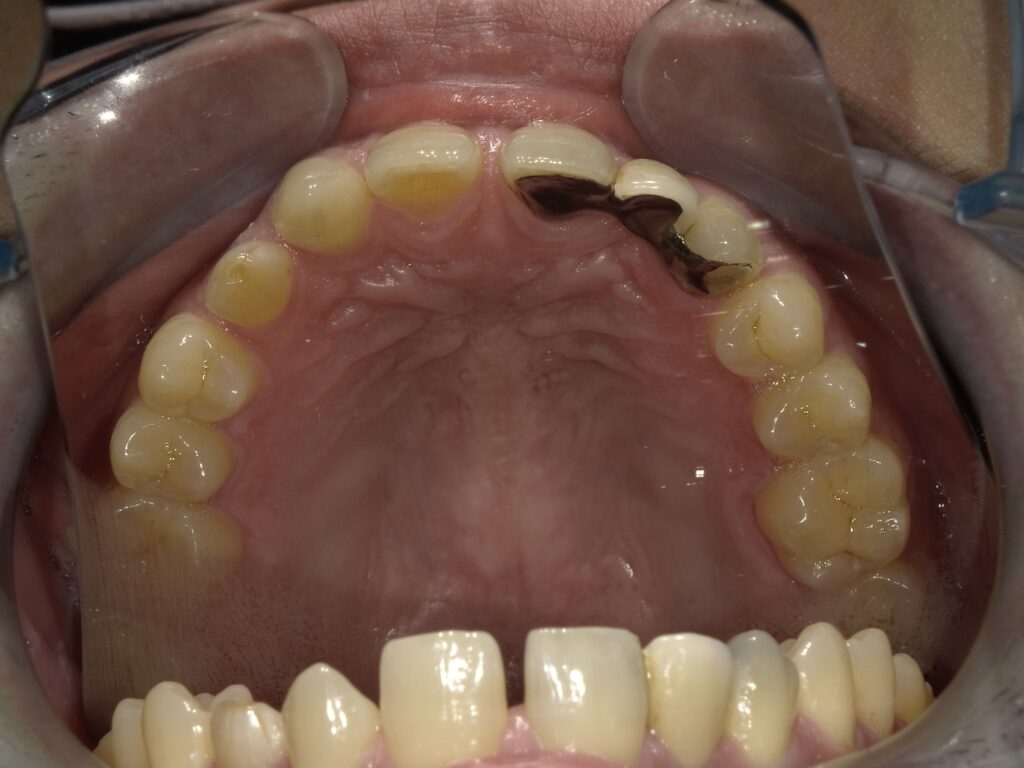

保険診療での接着ブリッジ(当院での自例)

当院で実際に保険診療で治療した方です。

前から2番目の永久歯がなく、乳歯が残っていた方で

それが抜けてしまったので治療を希望されました。

もう10年近く前の治療で、当時の保険診療では両隣の2本の歯を支えにしないと保険適応がありませんでした💦

歯科技工士さんに綺麗に作製してもらいましたが、裏の金属がどうしても透けて見えてしまうので隣の歯がやや黒くなってしまっています(・_・;

また、保険診療では両隣の歯に接着させないといけない時代でしたが、それぞれの歯が別々の動きをするのに裏で貼り付けているだけなので、片方が外れてしまうことが多く。。。

この方も数年して片方の接着剤が剥がれてしまって、1本の歯だけでくっついている状態ですが。

今のところやりかえもなく10年近くお口の中で使って頂いてます😃